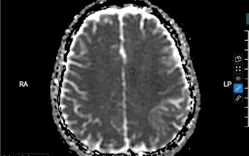

BS.CKI Vũ Văn Thoại, Khoa Nội Thần kinh, nhận định khả năng cao bệnh nhân mắc huyết khối tĩnh mạch nội sọ - một dạng đột quỵ hiếm gặp. Ngay lập tức, bệnh nhân được chỉ định chụp MRI sọ não có tiêm thuốc cản từ.

Kết quả cho thấy bệnh nhân vừa có nhồi máu não, vừa xuất huyết não, kèm hình ảnh huyết khối tĩnh mạch màng não vùng thùy đỉnh trái, xác nhận chẩn đoán ban đầu.